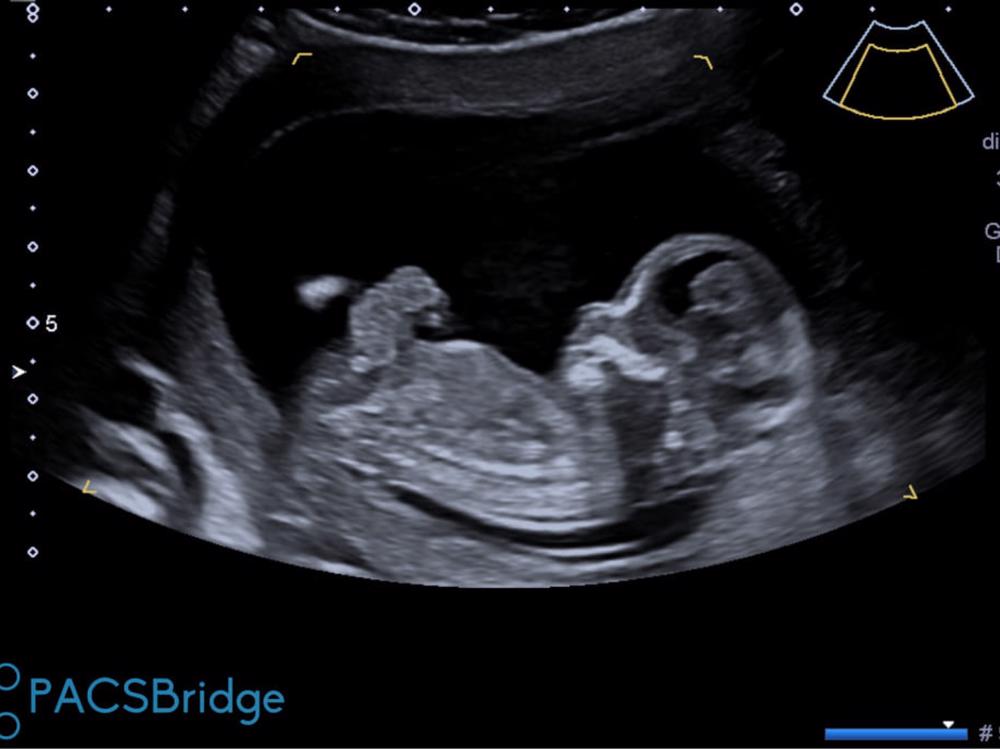

To support ongoing costs for baby Conroy diagnosed with Gastroschisis, where the intestines are formed outside of the body.

They found out at 12 weeks that my nephew has 'Gastroschisis' which means that his abdominal walls have not formed correctly resulting in his intestines growing outside his body. Once he is born he will be taken from my sister where the care for him will be immediate. He will go into surgery and have full closure within the first week to two weeks. His recovery will be a minimum of 4 weeks in Waikato hospital in NICU (2 hour drive from where they live) where my sister will be unable to spend the nights with him and will have to stay at a near by hotel. He will be monitored closely for infection and until his intestines are working how they should she wont be able to breastfeed or feed him herself.

My sisters first specialist appointment in Auckland at 16 weeks revealed another birth defect, it was believed he had talipes (club foot) due to the position of his feet in his 12 and 16 weeks scans, she had to have a amniocetesis test done as they were concerned there was an underlying chromosome or genetic issue. Thankfully the results came back clear and the 20 week scan revealed his club foot was just purely positional! The journey through all this took quite a toll on my sister and everyone close to her, we are all thankful there is only 1 birth defect to focus on and deal with.